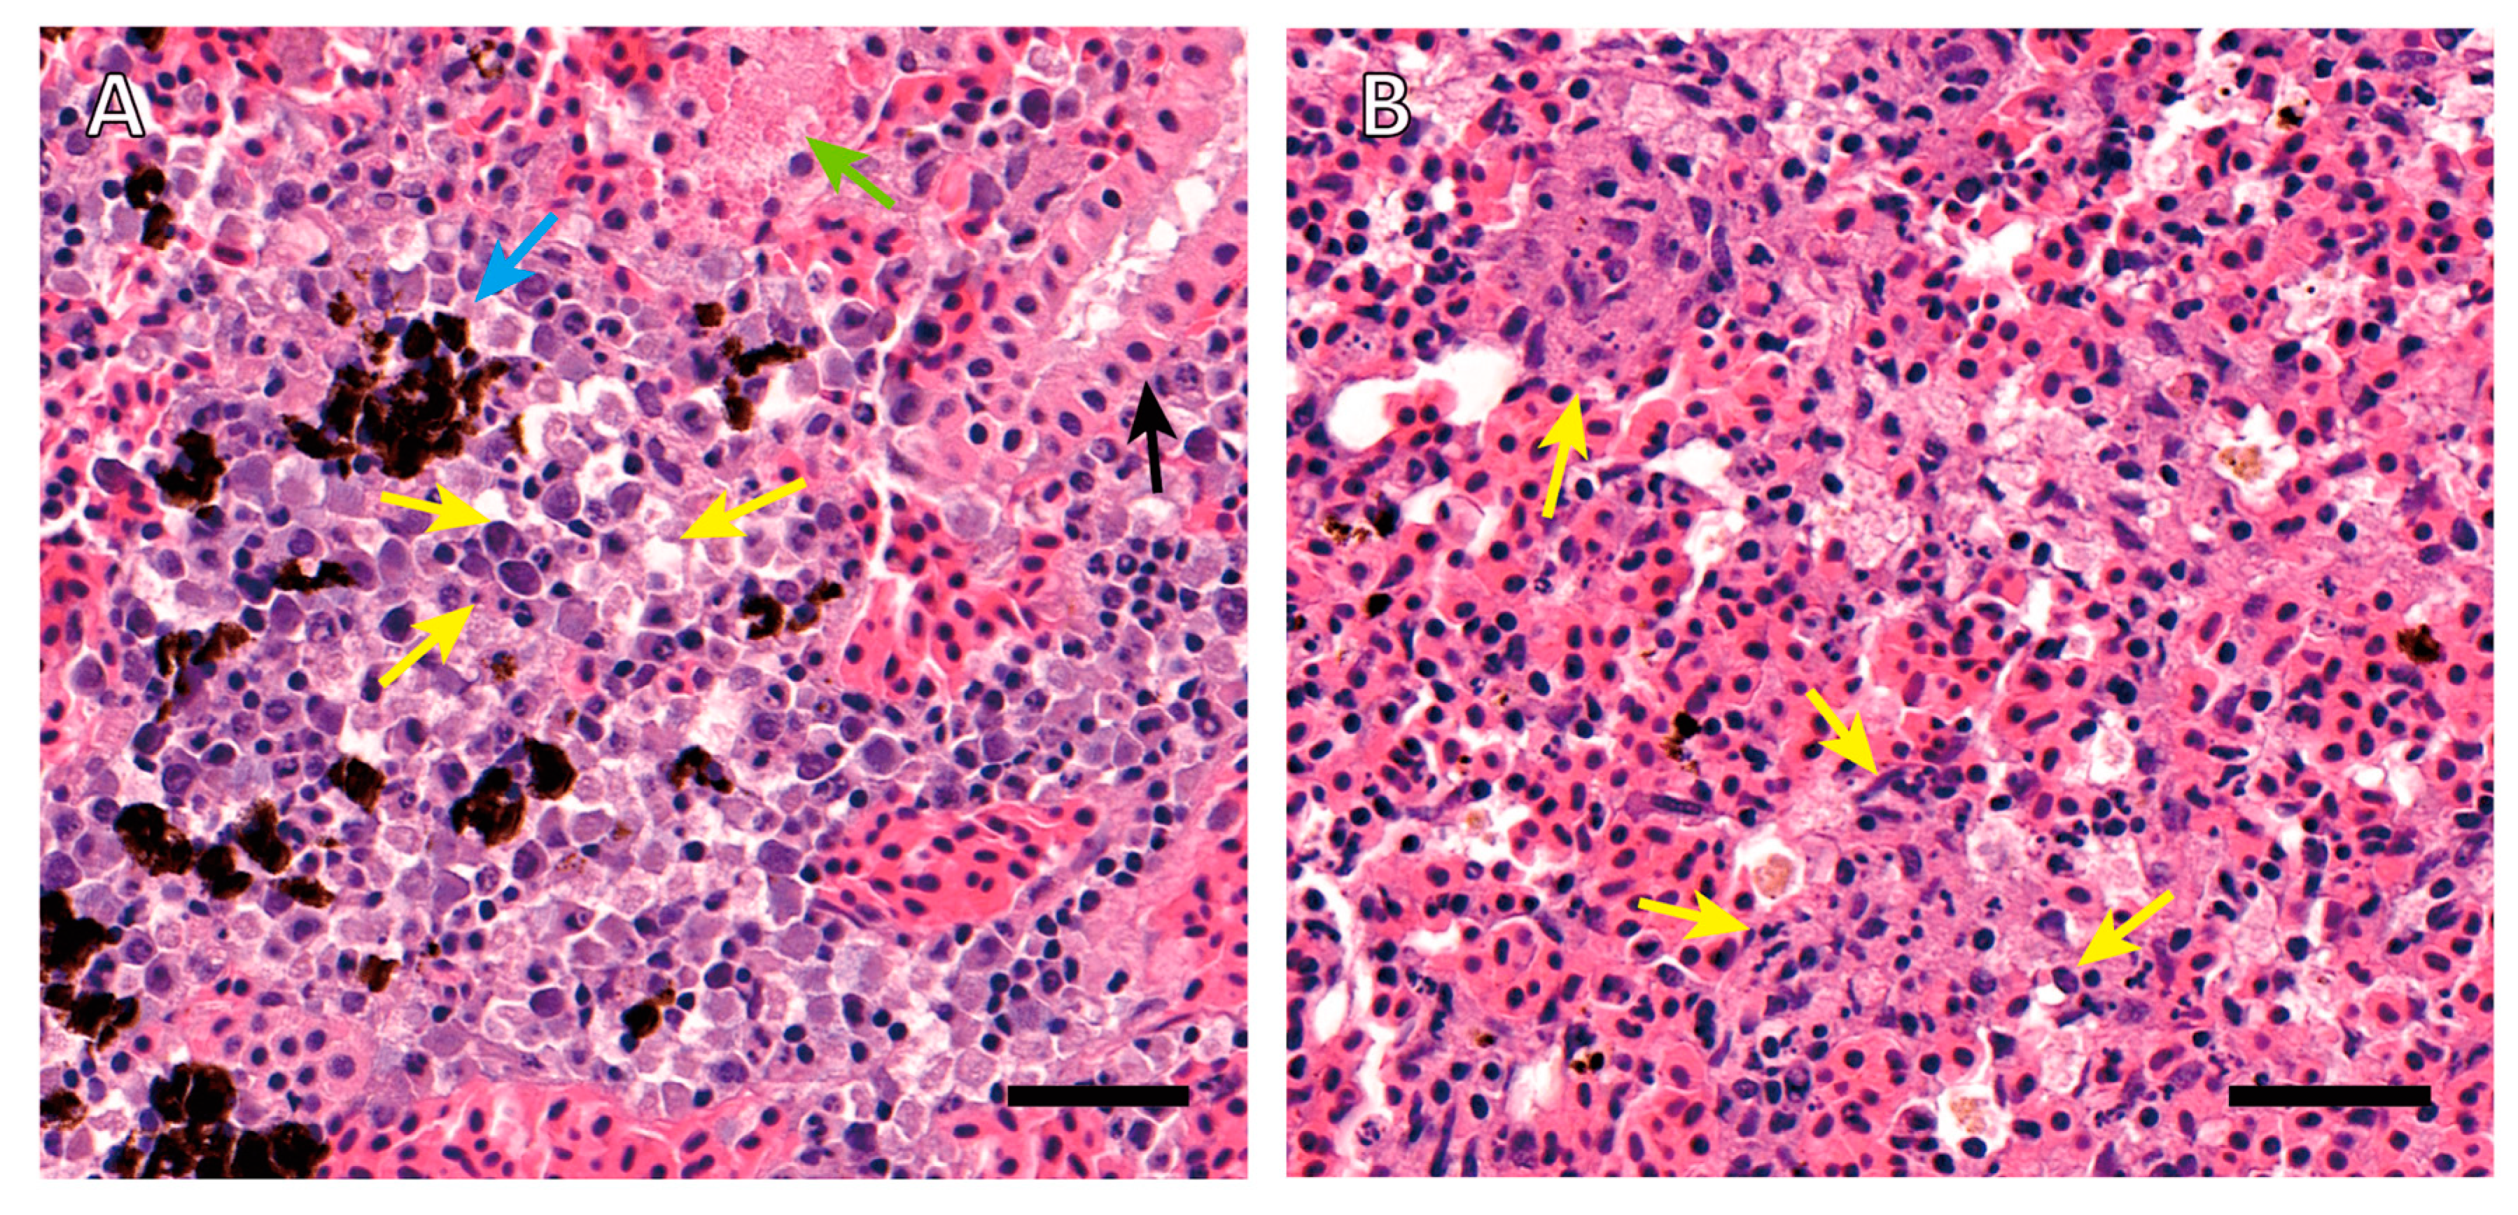

2.1.1. Histopathology